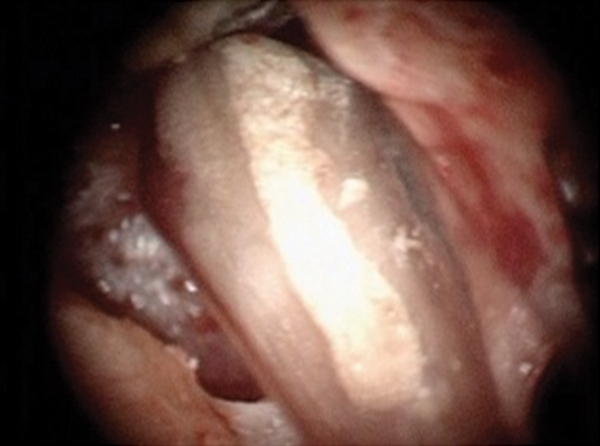

Fig 7. Preoperative pulp exposure after caries removal. Courtesy of Dr. Mohammed A. Alharbi.

Figure 7

Case 1: Direct Pulp Cap

Figure 6 shows the preoperative radiograph of an apparent carious exposure on tooth No. 19 of a 20-year-old male patient. A diagnosis of reversible pulpitis was made based on the history and clinical exam. After anesthesia and caries removal, the exposure was seen (Figure 7) and covered with BC RRM-Fast Set (Figure 8). After the BC base had fully set, a bonded resin was placed and a postoperative radiograph taken (Figure 9). At the 6-month follow-up visit, the tooth was asymptomatic and tested vital. Radiographically, no signs of pathology were noted (Figure 10).